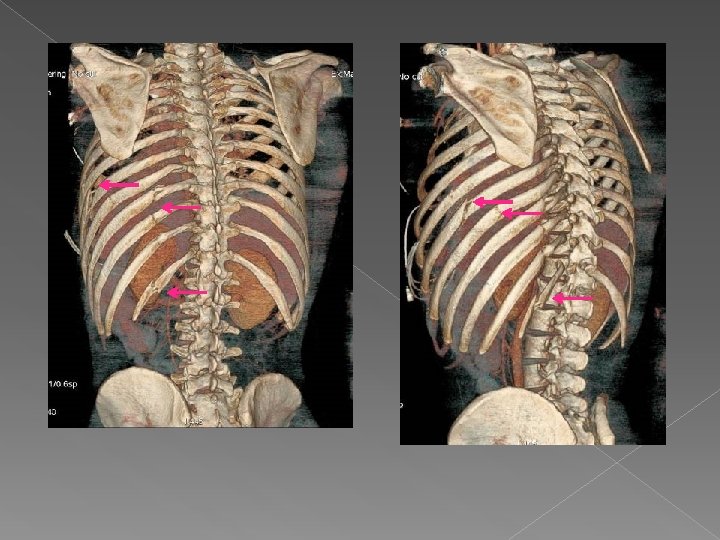

Caso 2 Varón de 32 años politraumatizado. Valor de VR: una visión rápida sobre

Caso 2 Varón de 32 años politraumatizado. Valor de VR: una visión rápida sobre las fracturas, en este caso costales, que pudiera tener el paciente.